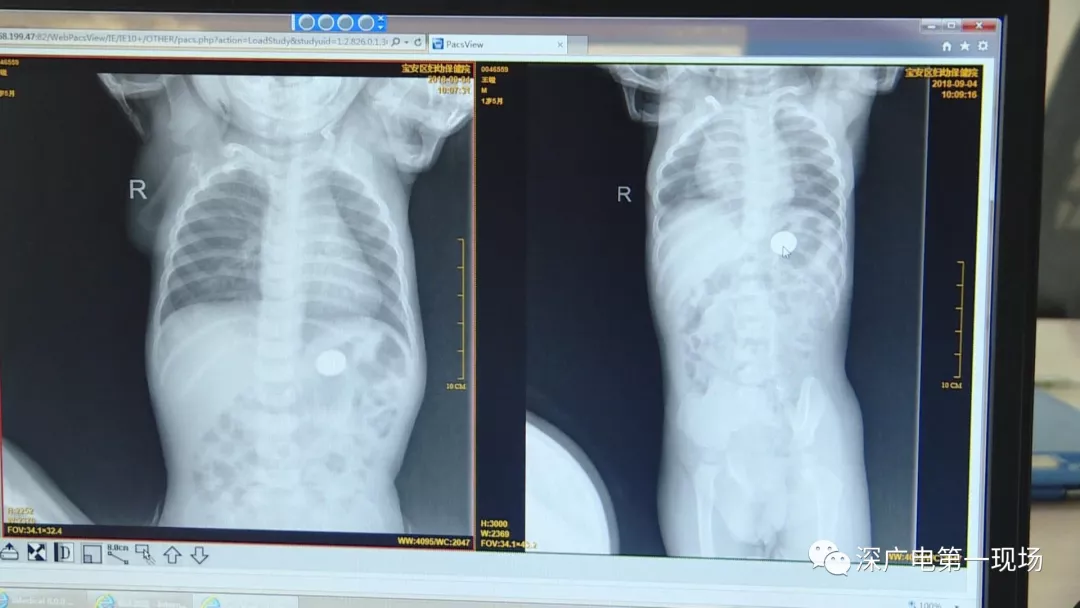

細(xì)心的醫(yī)生竟從

孩子的胸片中有了意外發(fā)現(xiàn)

9月4號,一名1歲零5個(gè)月的男嬰因在家中摔傷,被父母送到了寶安區(qū)婦幼保健院,醫(yī)生診斷為左側(cè)尺橈骨骨折。在進(jìn)行全麻手術(shù)之前,院方例行對嬰兒進(jìn)行了周身檢查。手術(shù)前,兒外科醫(yī)生趙冠聰在查看患者的胸片時(shí),發(fā)現(xiàn)這名嬰兒的胃部有一枚硬幣大小的暗影。

胃部取出一角硬幣

已吞咽半月之久

經(jīng)過兩個(gè)小時(shí)的時(shí)間,兒科醫(yī)生郭景濤為患兒取出了藏在胃底的一角錢硬幣。目前,患兒已經(jīng)痊愈出院。